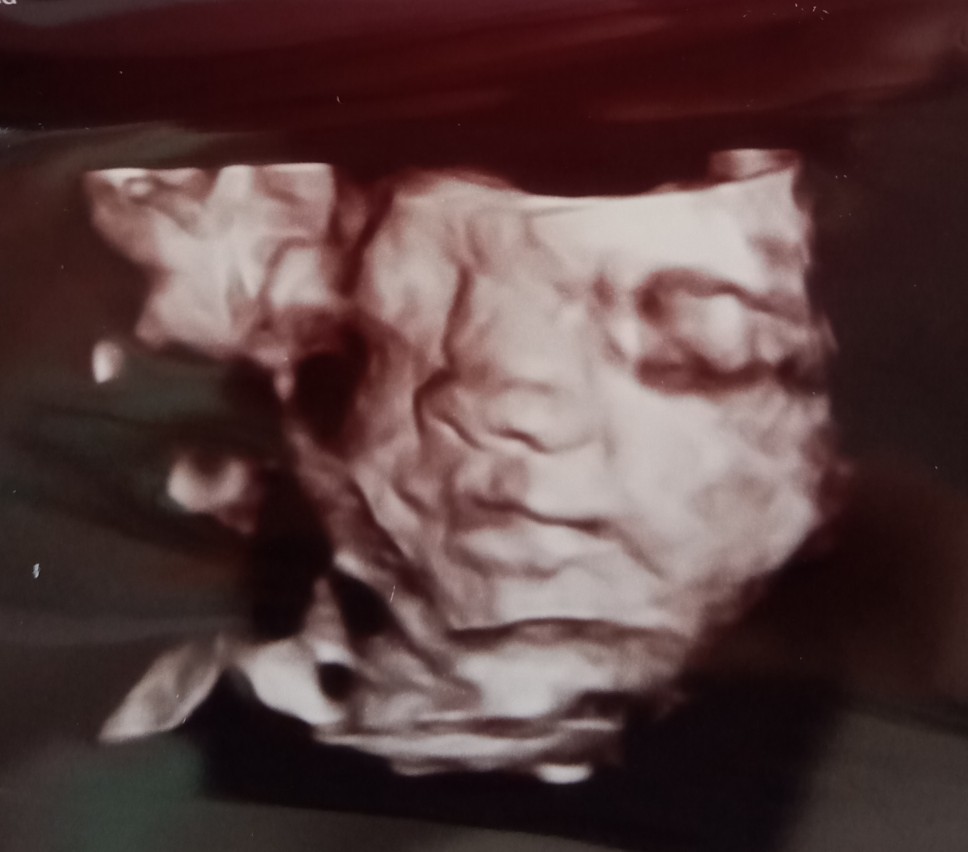

BABY SONGSANG 28MINGGU

Sy skrg pun 28week 5 hari br 2 hari lepas check up Dr ckp baby songsang tp nnti dah 9 bulan kepala baby akan pusing kebawah tu yg Dr ckp